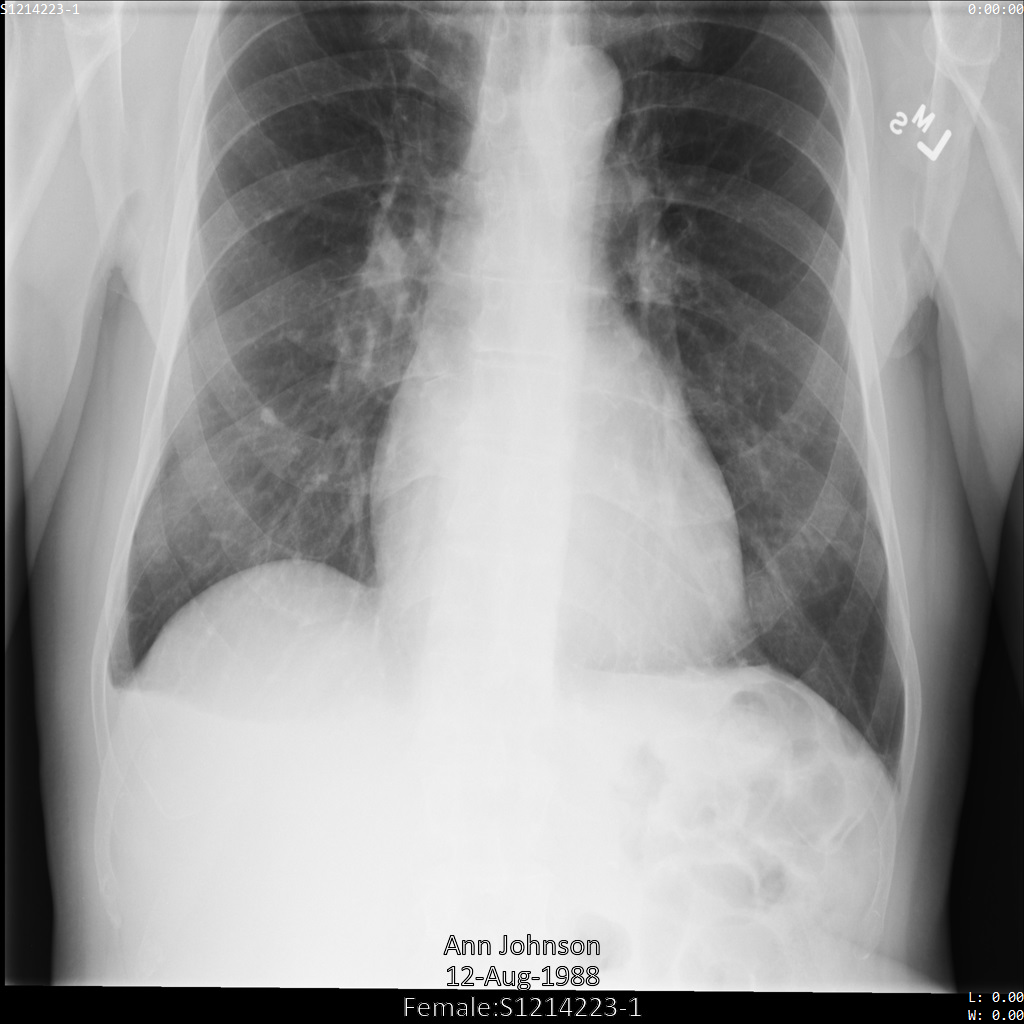

以下の各セクションでは、DICOM データを匿名化するさまざまな方法について、例を示しています。また、それぞれの例で匿名化された出力画像を示しています。各例では、入力として以下の元画像を使用しています。

各匿名化オペレーションからの出力イメージをこの元のイメージと比較して、オペレーションの効果を確認できます。

Cloud Healthcare API に画像を送信すると、画像は次のように表示されます。画像の上部隅に表示されているメタデータは削除されていますが、画像の下部にある焼き付き保護対象保健情報(PHI)は残ります。焼き付きテキストも削除するには、画像の焼き付きテキストを削除するをご覧ください。